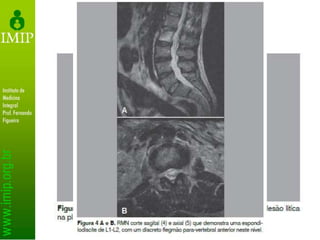

• Tomografia com ou sem contraste permite

melhor avaliação da lesão óssea e

comprometimento neural

• RNM facilita a distinção entre tuberculose

e tumor

– Presença de abscesso e fragmentos ósseos

Exames de Imagem •Radiografias primárias – Diminuição do espaço intervertebral – Osteopenia localizada • Radiografias tardias – Colapso em sanfona (Seddon) – Calcificação de partes moles

• 40.

Exames de Imagem •Identificação de cifose

Exames de Imagem •Tomografia com ou sem contraste permite melhor avaliação da lesão óssea e comprometimento neural • RNM facilita a distinção entre tuberculose e tumor – Presença de abscesso e fragmentos ósseos